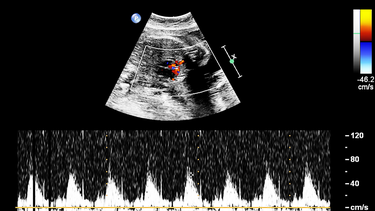

Để có kết quả chính xác hơn, chị em nên đến cơ sở y tế để làm xét nghiệm máu vì phương pháp này có độ chính xác cao hơn. Bên cạnh đó, siêu âm cũng có thể giúp xác định vị trí thai nhi, từ đó loại trừ trường hợp mang thai trứng hoặc thai ngoài tử cung. Khi đã có chẩn đoán chính xác, bác sĩ sẽ hướng dẫn chị em các bước tiếp theo, bao gồm lịch khám thai định kỳ và các xét nghiệm tầm soát quan trọng để đảm bảo thai kỳ phát triển khỏe mạnh.